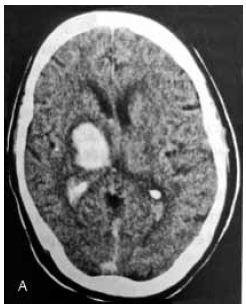

Paciente de 61 anos, admitido no pronto-socorro com duas horas de início de hemiplegia completa à esquerda. Sinais vitais na admissão: Pressão arterial 200/120 mmHg, glicemia capilar 134 mg/dL. Tomografia de crânio sem contraste abaixo. Assinale a alternativa correta referente a este caso clínico.